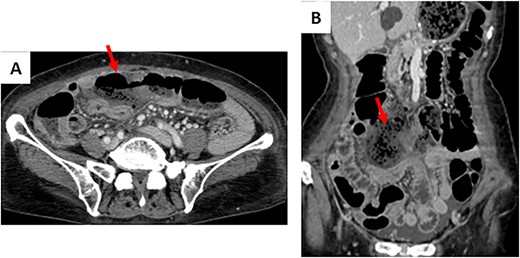

The patient drank water the first day after surgery and resumed oral intake on the second day after surgery. On the morning of the third day after surgery, she developed lower abdominal pain and 38°C fever. Abdominal contrast-enhanced CT demonstrated that the continuity of the transverse colon wall was interrupted. Abscess formation with a surrounding stool mass was suspected (Fig. 2). Therefore, emergency laparotomy was performed.

Contrast-enhanced CT on the third day after the primary operation. (A) The continuity of the transverse colon wall was interrupted. (B) Abscess formation was suspected with a surrounding stool mass.